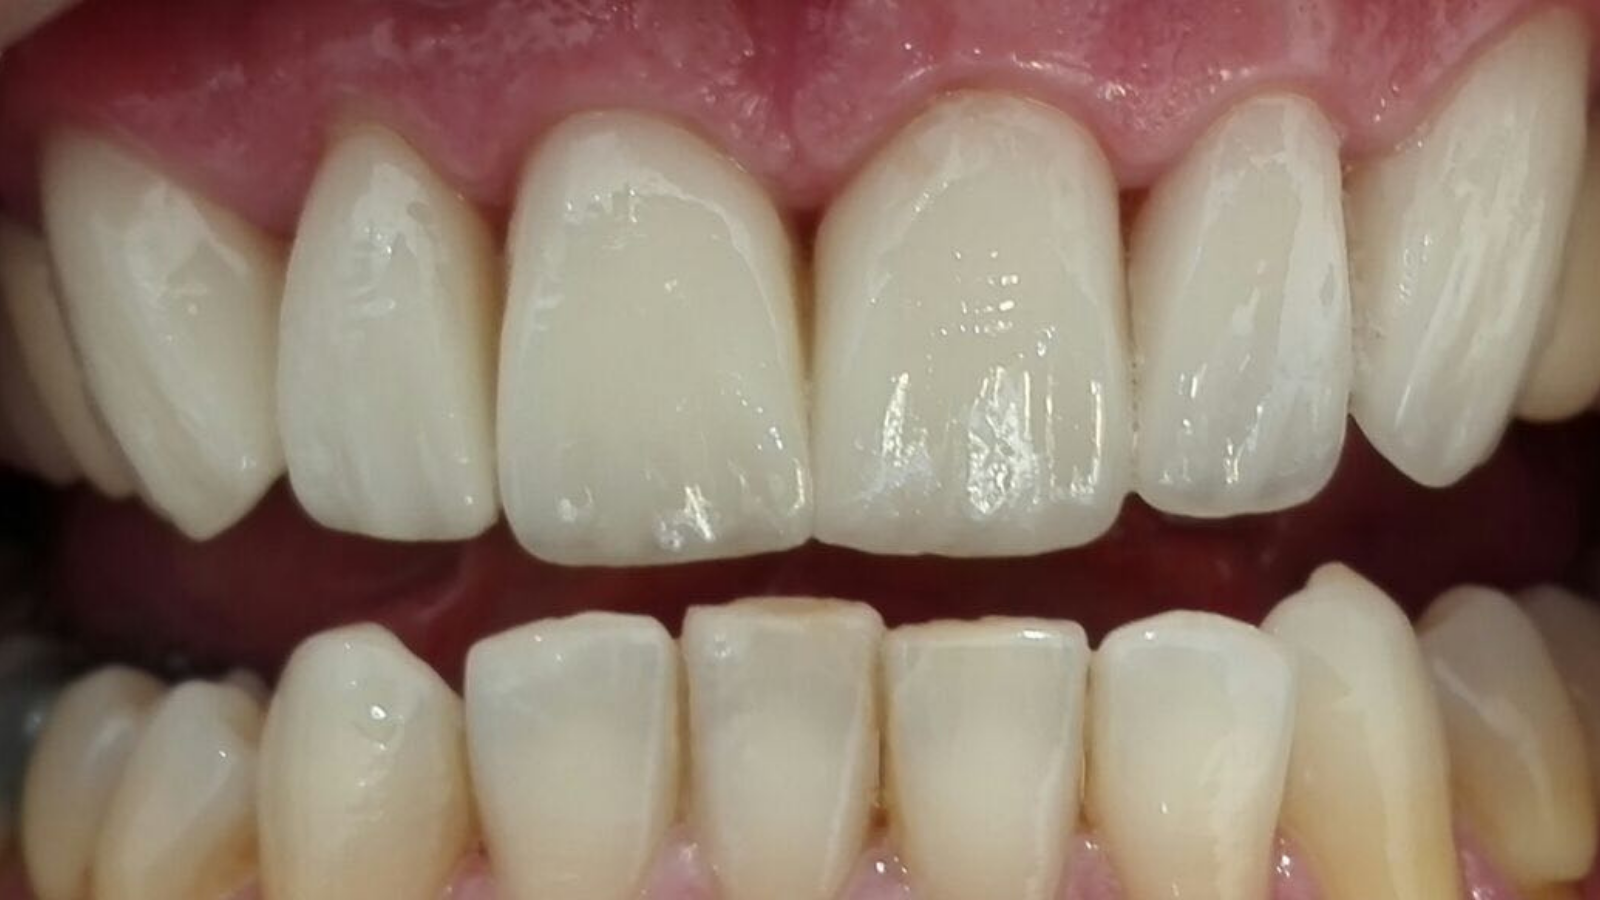

Facettes de canine à canine : sourire plus harmonieux et naturel

Un patient se présente pour rendre son sourire plus harmonieux. Les images “Avant” montrent un secteur antérieur avec une esthétique perfectible, notamment au niveau de l’homogénéité, des contours et du rendu de surface.

La prise en charge a consisté en des facettes de canine à canine, avec un objectif clair : retrouver un résultat naturel avec de la brillance, du relief et de la translucidité.

Les images “Après” mettent en évidence un sourire plus équilibré, avec une meilleure continuité entre les dents, un rendu plus lumineux et une texture plus réaliste.

Images :